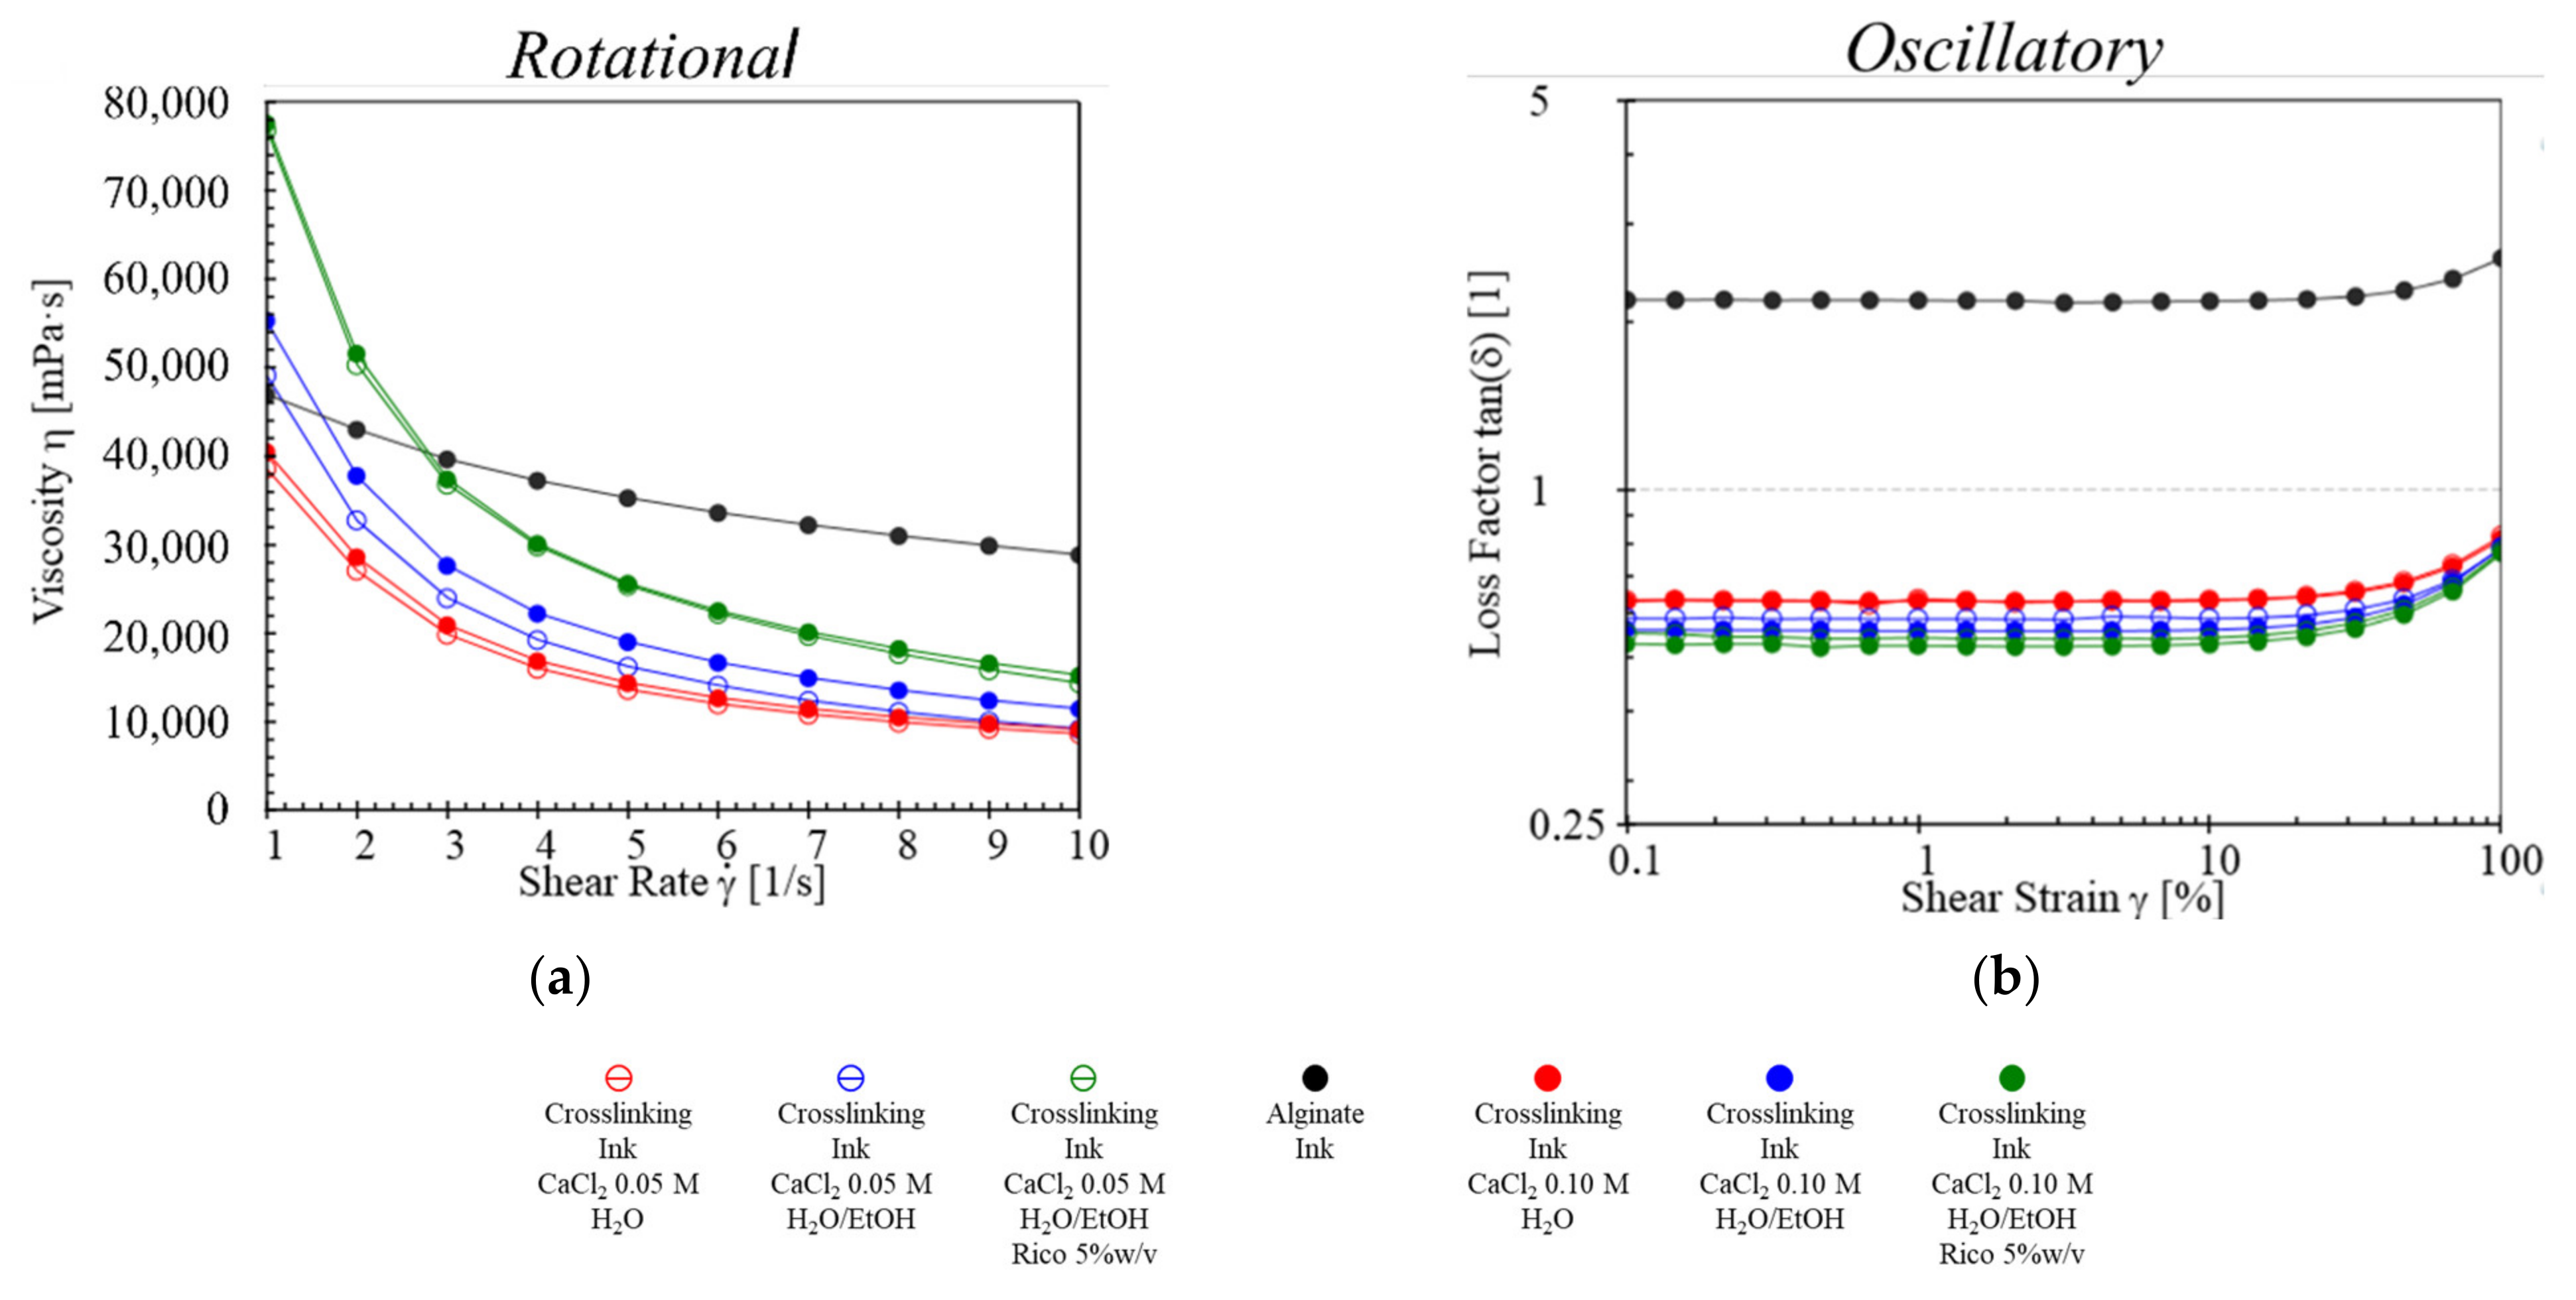

2.2. Rheological Studies

4.2.2. Rheological Study